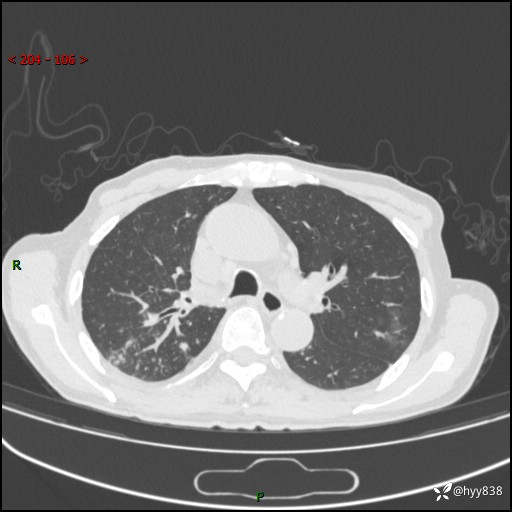

一个月后第二次CT检查(常规抗感染,患者不配合:增强、住院---)